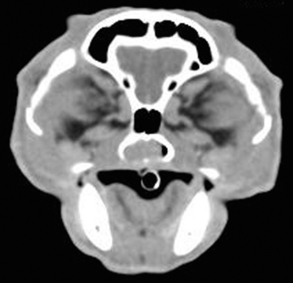

Radiography

Radiographic imaging or CT is always performed before rhinoscopy. Rhinoscopic iatrogenic hemorrhaging and irrigation fluid used during the procedure will distort tissue and create fluid densities that can influence the findings in any radiographic study. Nasal radiographs can be performed in most hospitals and, with practice, can be very useful in the localization and characterization of nasal and nasopharyngeal disease.5 Nasal radiographs require general anesthesia and special patient positioning. Most commonly performed are 30-degree beam-angled open-mouth ventrodorsal and straight lateral views. The open-mouth view provides a complete, symmetrical image of the nasal cavity without superimposition of the mandible. Tumors typically show asymmetrical opacities and turbinate destruction (Figure 19-6). Turbinate destruction is also seen with fungal rhinitis. The straight lateral view allows evaluation of the nasopharynx and frontal sinuses (Figure 19-7). Further study of the frontal sinuses is achieved with a rostrocaudal tangential view (Figure 19-8). This allows comparison of the left and right frontal sinuses as the cavities are superimposed on the lateral view. Dental films of the maxillary arcade are sometimes needed to rule out tooth root abscesses and oronasal fistulae. MRI and CT scans are becoming more commonly available and provide better detail of the nasal, nasopharyngeal, and sinus cavities and cranial vault anatomy compared with standard radiography.6,7 Advanced imaging via MRI and CT, although considered state of the art, assist in description and localization of diseased tissue but have not yet produced results specific enough to eliminate the need for rhinoscopy8,9 (Figures 19-9 through 19-11) (Table 19-1).

image

Figure 19-9 Feline skull computed tomography image with nasopharyngeal mass.